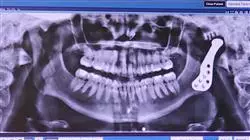

人体的功能就像一台机器一样。只要一个齿轮出现故障,系统就会受损,这可能导致严重的错误。这个例子完全适用于颌面生理学。在这种情况下,牙齿骨骼畸形除了产生许多病人所要求的非常高的美学反响外,还影响到其他的病症,对降低他们的生活质量产生影响,例如,在治疗睡眠呼吸暂停或影响颞下颌关节时,颞下颌关节在许多基这个的身体功能,如吃饭、说话或面部表情中起着基础作用。

为此,为了向这一医学领域的专家提供一种资格,使他们能够获得广泛的知识和最新的战略和技术来干预患有这种疾病的病人,TECH开发了这门完整的牙颌骨病理与颞下颌关节病理课程。